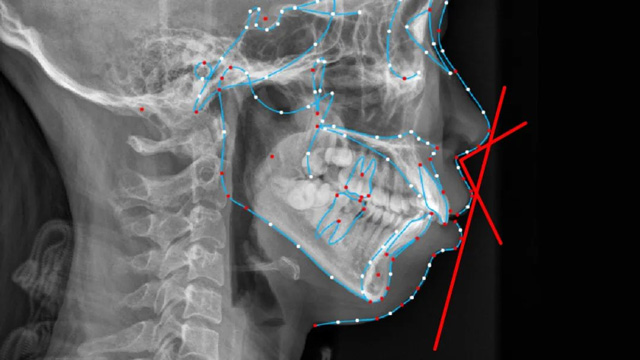

韩汉主任:一个人的下巴是否美观,从颌面部美学来说有具体的指标可以去衡量,包括下巴在垂直向的高度(正面),矢状向的长度(侧面),以及从侧面看鼻子、嘴唇和下巴之间的角度关系,还有下巴颏部的骨骼形态是否饱满。

在口腔正畸学中,根据下颌骨与颅底之间的关系划分有三种对应的面型:高角面型、低角面型和均角面型,高角对应的是长窄脸型,中下庭较长,低角对应的是短方脸型,比如国字脸,比较理想的是均角面型。